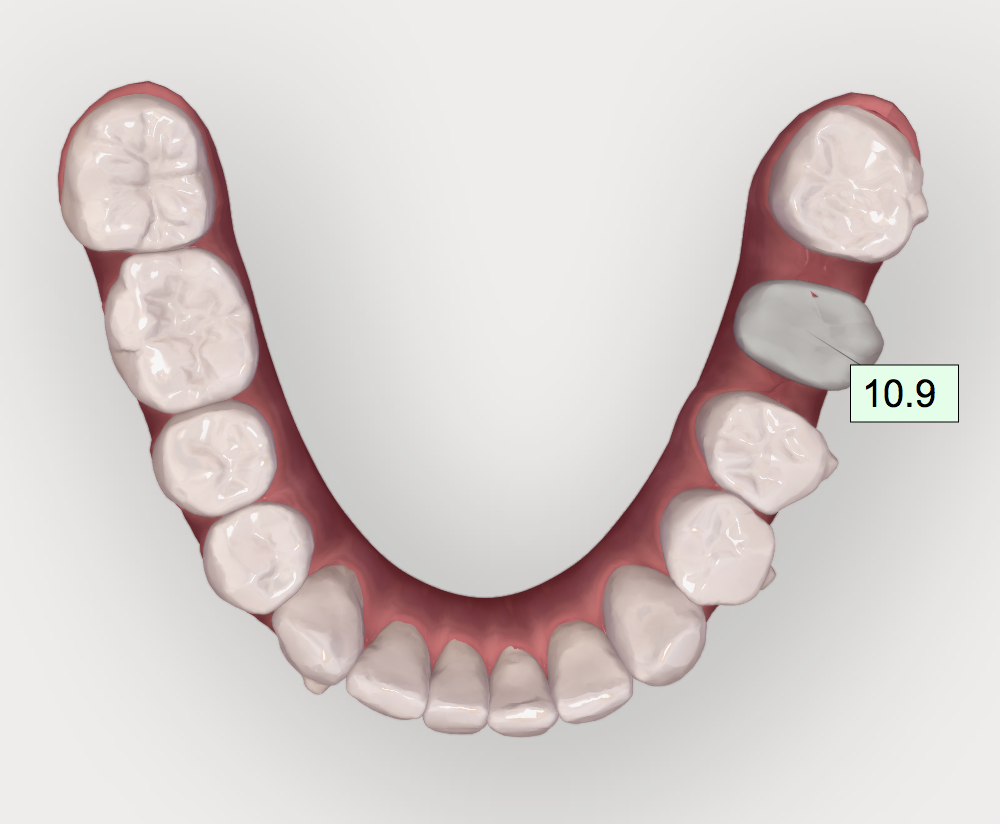

• Minimally invasive preparation. Teeth should be restored using minimally invasive tooth reduction and placement of margins in enamel. Aligning and leveling the cementoenamel junctions of the teeth with orthodontics before restorative preparation minimizes the need for crown reduction and possibly eliminates the need for crown lengthening. In this manner, the treatment no longer has to focus exclusively on the incisal edges. Instead, it can correct the differential extrusion with differential intrusion. For this case, differential intrusion of the anterior teeth was incorporated into removable aligners to level the patient's cementoenamel junctions (Figure 4).

(4.) Postorthodontic anterior bite.

Figure 4